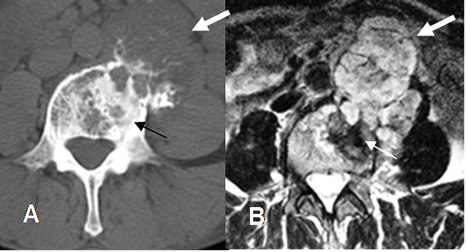

Fig 93 A. Condrosarcoma.

A: TAC axial y B: RM axial en T2. Lesión vertebral mixta, con componente lítico y esclerótico. (Flechas delgadas). Hay masa de tejidos blandos de comportamiento agresivo y que crece anteriormente (Flechas gruesas), por condrosarcoma.

Fig 93 B. Condrosarcoma.

A: RM axial en T1 y B: RM coronal en T2. Gran lesión heterogénea y lobulada en relación con el hueso iliaco, de predominio hipointenso, que corresponde a condrosarcoma.